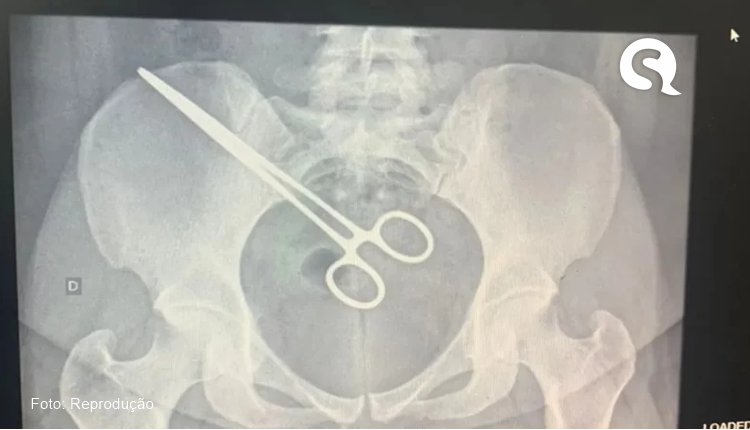

A Santa Casa de Araçatuba, no interior de São Paulo, apura a conduta de médicos que esqueceram uma pinça cirúrgica dentro do corpo de uma paciente após uma cirurgia. Ela teria descoberto o objeto, muito parecido com uma tesoura, ao visitar o marido em um presídio e passar por um detector de metais.

Em seguida, a mulher foi até a Santa Casa e confirmou que a pinça estava em sua região pélvica. No mesmo hospital, ela havia feito uma cirurgia em setembro.